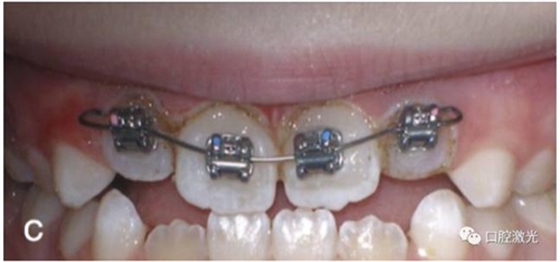

正常情況下,理想的托槽粘接位置為牙冠的中心位置。如果要達到這一目的,正畸牙醫(yī)首先需要能夠從視覺上觀察清楚牙冠的整體形態(tài)。如果存在牙齦覆蓋、遮擋的情況,就很難達到這一目的。這時,簡單的激光牙齦切割就可以很好的增加牙冠的暴露程度,達到更加準(zhǔn)確的粘接托槽的目的,從而也就加快了整個正畸療程的速度。通過下圖的病例可以看到,不僅患者節(jié)約了數(shù)月的等待時間,同時也創(chuàng)造了一個干凈的口腔環(huán)境,降低了在后續(xù)的正畸治療中可能導(dǎo)致牙齦增生的風(fēng)險。

治療前

激光牙齦切割后暴露更多的上前牙便于粘接托槽

當(dāng)天粘接托槽后即刻

4周后即可見明顯效果